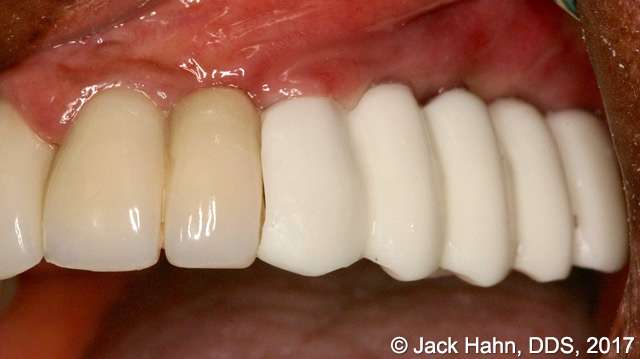

CASE #5 Laser Implant Exposure After Healing Abutments Come Off

This patient’s healing abutments came off in between appointments. In order to place the prosthesis, Dr. Hahn had to re-expose the implants. The photos were taken immediately before the exposure, immediately after the exposure, and after the placement of the prosthesis.

Implant exposures with LightScalpel dental lasers are quick and easy, saving Dr. Hahn valuable chair time. Some other benefits of performing Dental implant exposures with a LightScalpel laser include: it’s excellent coagulation ability; improved healing; minimized damage to surrounding tissues; diminished inflammation, swelling and pain; reduced risk of infection; and good patient acceptance.